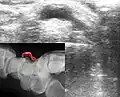

Ультразвуковое и рентгенографическое (на врезке) изображения гигромы запястья